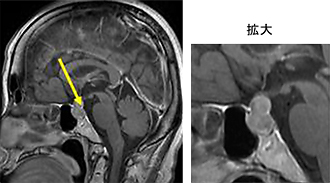

ラトケ嚢胞

ラトケ嚢胞とは

ラトケ嚢胞とは脳下垂体にできる袋状のできものです。この下垂体には様々な腫瘍が発生することがあります。かたまりとしてできるものと袋状になってできるものがあり、ラトケ嚢胞は袋状のできものの代表です。

ラトケ嚢胞とは脳下垂体に生じた粘液を含んだ嚢胞です。

袋が大きくなると下垂体の上にある視神経(物を見るための神経)を圧迫して目がみえなくなります。

また、袋が正常下垂体を圧迫したり、袋の中の粘液が下垂体に炎症をおこして下垂体ホルモン分泌が低下することがあります。